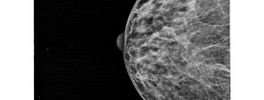

Mammograpgy-Normal

Mammography -Breast Tumor

Mammography -Normal

Mammography-Breast Tumor